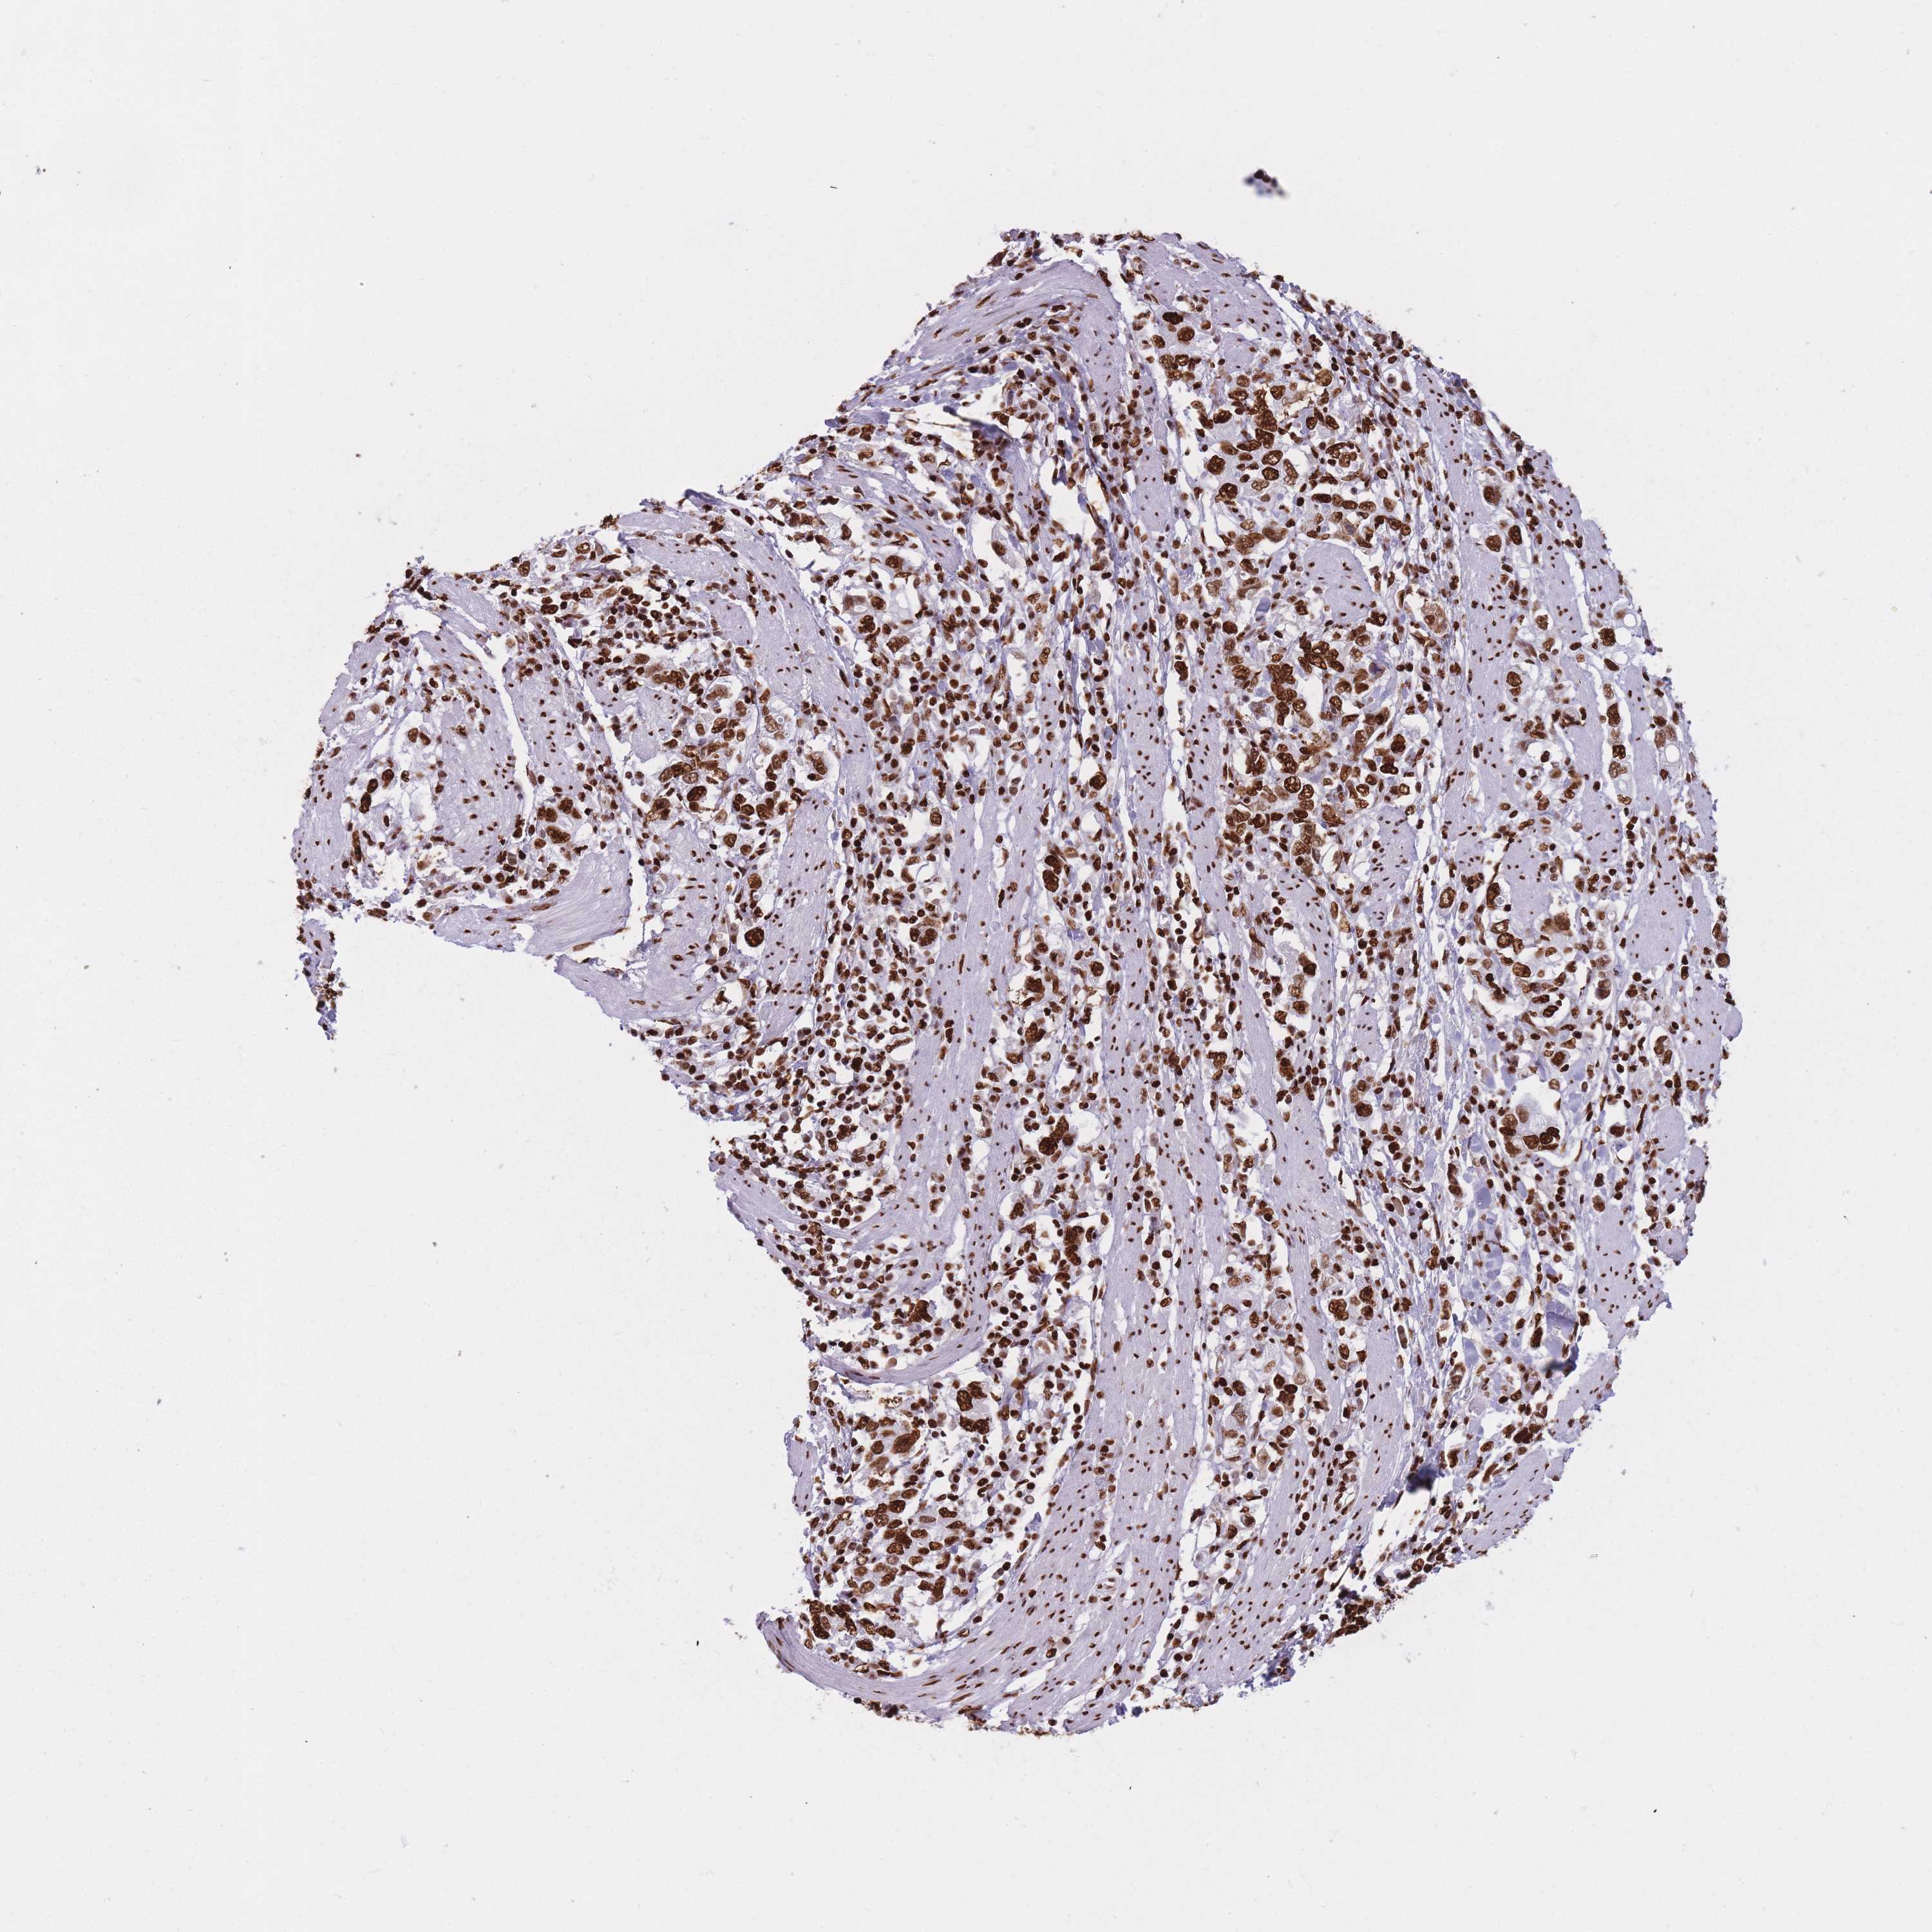

STOMACH CANCER - Protein expressioni

A mouse-over function shows sample information and annotation data. Click on an image to view it in a full screen mode. Samples can be filtered based on level of antibody staining by selecting one or several of the following categories: high, medium, low and not detected. The assay and annotation is described here.

Antibody stainingi

Antibody staining in the annotated cell types in the current human tissue is reported as not detected, low, medium, or high, based on conventional immunohistochemistry profiling in selected tissues. This score is based on the combination of the staining intensity and fraction of stained cells.

Each image is clickable and will lead to virtual microscopy that enables deeper exploration of all samples and also displays staining intensity scores, fraction scores and subcellular localization as well as patient and tissue information for each sample.

Antibody HPA046290

Antibody HPA049475

Antibody CAB046477

Staining

High

Medium

Low

Not detected

Intensity

Strong

Moderate

Weak

Negative

Quantity

>75%

75%-25%

<25%

None

Location

Nuclear

Cytoplasmic/membranous

Cytoplasmic/membranous,nuclear

Adenocarcinoma, NOS